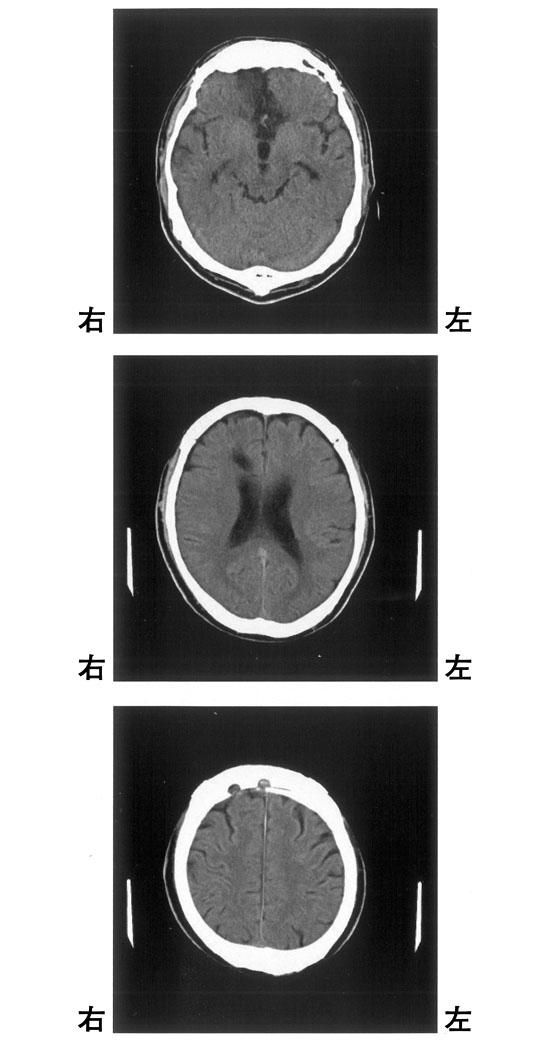

56歳の男性。発症時に明らかな運動麻痺はないが、歩くとすぐによろけて物につかまっていないと立っていられなくなり、頭部CT検査で脳出血と診断された。頭部CT画像を示す。この患者の頭部CT画像として最も可能性が高いのはどれか。

1

①

2

②

3

③

4

④

5

⑤

CT(①~⑤)を別に示す。片麻痺を呈する可能性が高いのはどれか。2つ選べ。